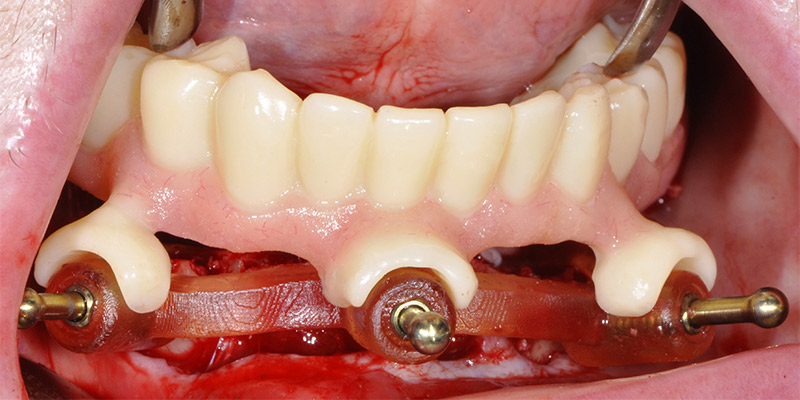

Fig. 30 : enfin, la restauration transitoire est empilée sur le guide de résection pour être solidarisée en bouche aux gaines provisoires vissées sur les piliers.

(NDLA : l’intervention est réalisée sous AG selon la volonté de la patiente ; le temps, en particuliers pour les photos, est compté par les obligations de l’anesthésie ; sans s’en apercevoir la restauration a bougé lors de la prise de la photo et ne reflète pas la réalité de la parfaite adaptation des pièces).

Fig. 31 et 32 : l’assemblage entre la restauration PMMA et les gaines en titane est réalisé avec une colle composite.

Fig. 33 et 34 : la finition est immédiatement et rapidement réalisée au fauteuil pour une mise en place de la prothèse transitoire dès la fin de l’intervention.